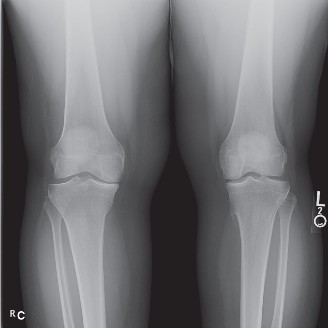

CASE 4 A 54-year-old skier injures his right knee on the last run of the day. He describes getting his ski stuck in the snow and having an immediate onset of pain on the inside of his knee. He did not hear a pop and was able to make his way down the slope under his own power. Over the last few days, the pain has been worse when bearing weight. X-rays are shown in Figure 9–4A–C.

Figure 9–4 A–B